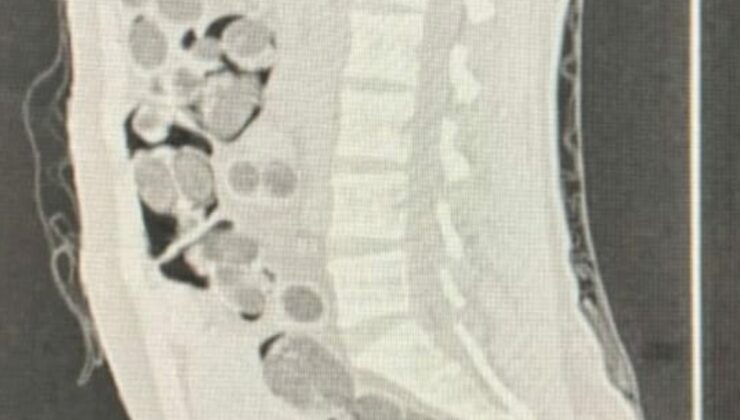

Şüpheli, uyuşturucuyu teslim edeceği yine yabancı uyruklu alıcıyla buluştuğu sırada düzenlenen operasyonla suçüstü yakalandı. Gözaltına alınan iki zanlı, detaylı kontroller için Denizli Devlet Hastanesi’ne götürüldü. Yapılan röntgen incelemesinde, şüphelinin midesinde 219 paket halinde saklanmış uyuşturucu madde tespit edildi.

Midesinden doğal yollarla çıkarılan 1 kilo 144 gram skunk, 178 gram metamfetamin, 90 adet uyuşturucu hap ve 7 gram afyon sakızı, ekipler tarafından ele geçirildi. Emniyetteki işlemlerinin ardından iki şüpheli tutuklanarak cezaevine gönderildi.